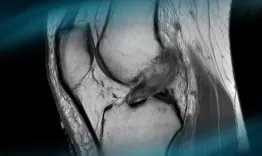

Arthrosopic arthrolisis for knee stiffness after ACL reconstruction can be challenging. You can find in this video the technique proposed by Etienne Cavaignac for anterior and posterior arthrolisis.

All-Arthroscopic anterior and posterior arthrolysis for extension deficit after ACL reconstruction

The goals of this clinical case are to discuss the physical examination of a multiligament knee injury and its surgical treatment.

Management of a chronic multiligament knee injury

The goals of this clinical case are to discuss the different therapeutic options in cases of ACL graft failure, and to propose an innovative technique.

Management of an ACL graft failure done by Harmstrings

Accurate and timely diagnosis of lateral meniscus radial tears is crucial. These tears disrupt circumferential fibers, impairing meniscal function and joint stability. Often underdiagnosed on imaging, they require careful arthroscopic evaluation when suspected.

Radial tear

Multiligamentous injuries are technically demanding. This video demonstrates a fully arthroscopic technique for posterior cruciate ligament and posterolateral corner reconstructions.

Combined anatomical arthroscopic posterior cruciate ligament and posterolateral corner reconstruction using a knotless anchor: a simplified approach